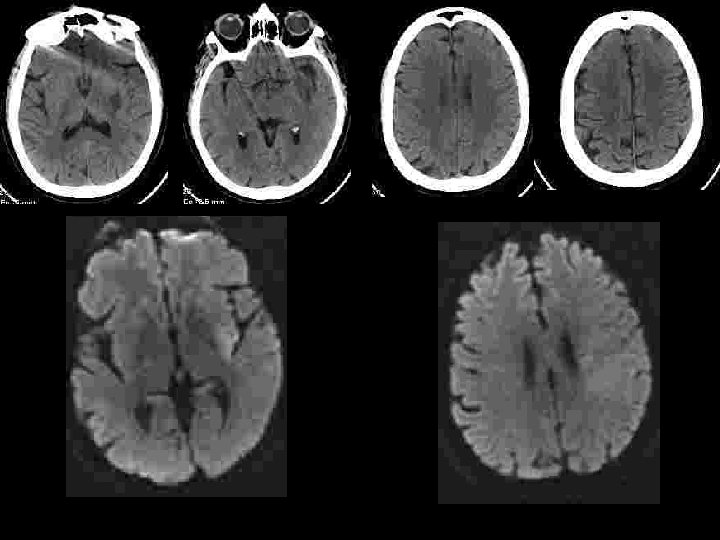

Sélection des patients • Être efficace : y a t’il du parenchyme a sauver ? – Diffusion : nécrose définitive! discutable: • diminution des zones d’anomalies de diffusion après thrombolyse IA • Hétérogénéité des niveaux de baisse d’ADC à l’intérieur de la zone anormale • diminution progressive de l’ADC de la périphérie vers le centre: notion de seuil? – < 50 % : évolution vers la nécrose certaine – >70 -80% : récupérable si recanalisation – Importance de l’évaluation de l’ischémie: • collatéralité en angiographie • perfusion en IRM ou en scanner

Sélection des patients imagerie • Efficace – – Est ce un AVC? Ischémique ou hémorragique? Mismatch? Occlusion persistante? • Rapide < 15 minutes Time is brain!! – MRI: Diffusion+3 d TOF MRA+ Perfusion. MR – CT scanner+angio CT+ perfusion CT

Sélection des patients • Ne pas être dangereux: identifier les patients à haut risque d’hémorragie – Localisation profonde – Délai – Baisse de l’ADC: risques si ADC< 33% – Hypoperfusion sévère : CBF< 33%

Sécurité • La sélection sur l’IRM augmente t’elle la sécurité de la thrombolyse? – Ringleb et al JNNP 2007; 78: 690 -693 • 90 octogénaires • Hémorragies 9, 4% avec CT , 0 avec IRM • 0 influence sur l’évolution globale – Schellinger et al Stroke 2007 • 1210 patients (CT<3 H: 714, MRI<3 h: 316, MRI >3 h: 180) • Hémorragies symptomatiques : 5, 3%, 2, 8% et 4, 4% • mortalité: 13, 7% vs 11, 7% avant 3 h • Influence sur le taux d’évolution favorable après 3 h